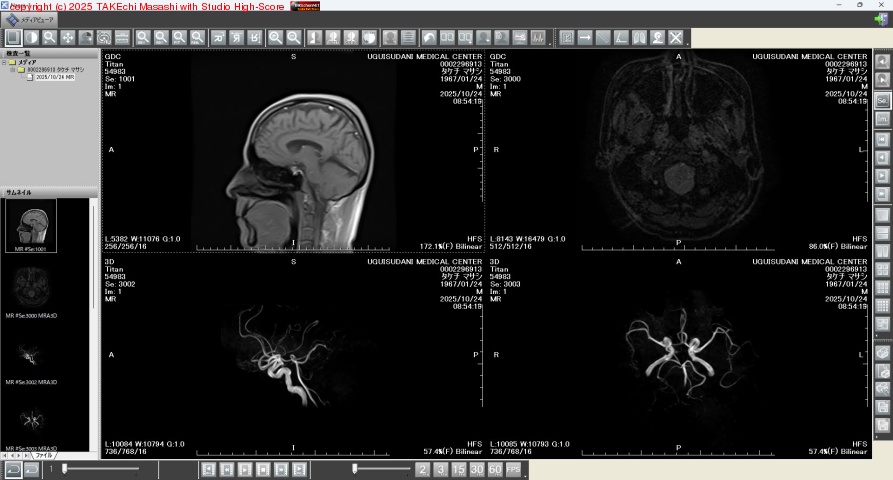

先日の健康診断,脳ドック MRI 画像 CD-ROM が届いたけど,専用ビューアアプリの使い方が全くもってワカラン! // 脳ミソかろうじて詰まっている事はワカッタ